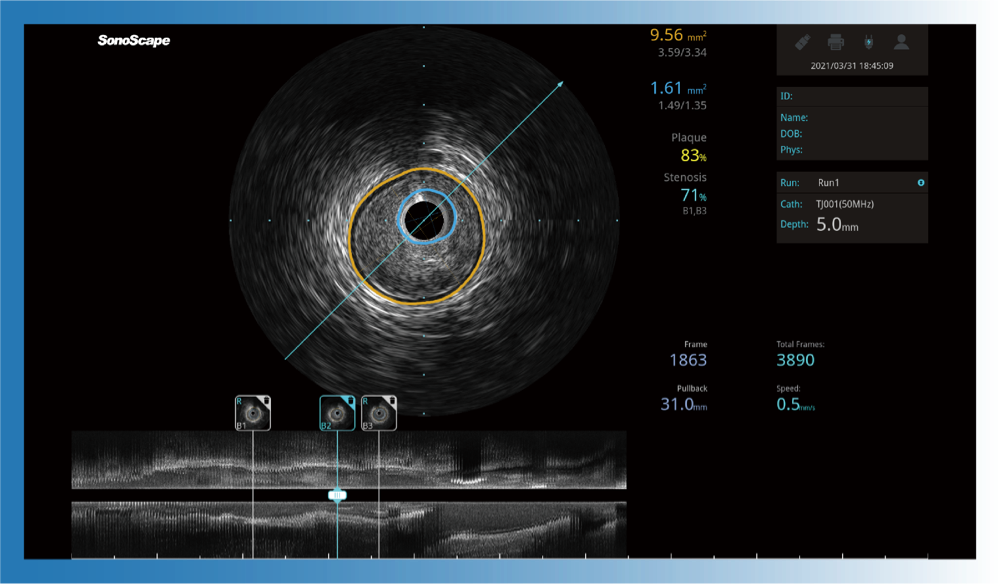

一键智能描迹,自动测量斑块负荷、面积狭窄率等指标,准确率高于90%

治疗前后两次测量录像对比

简化疗效评估